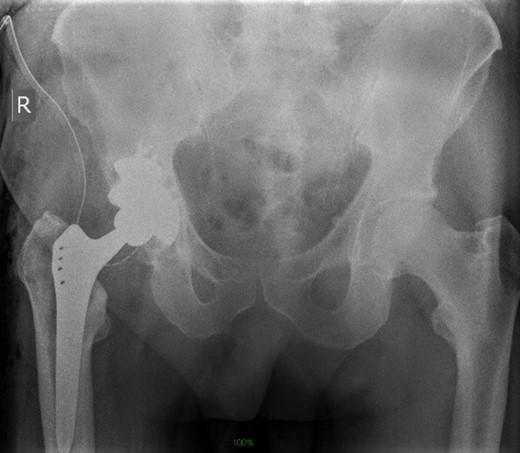

The surgery was uneventful and a trabecular metal cup with semilunar augment were implanted (Zimmer, Warsaw, IN). The femur was reconstructed with a cementless Alloclassic stem (Fig. 8)